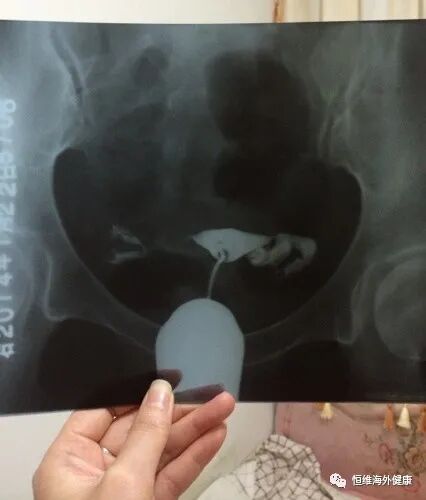

有位女性患者因多年前做过腹腔镜下双侧输卵管造口的手术,试孕了一年没有成功,继而到我们辅助生殖中心做试管。

当时在促排卵的时候B超发现输卵管积水,医生建议她全胚冷冻,处理好积水再来移植。

刚开始患者的确是不能理解,也无法接受切除输卵管,直到经历过2次取卵,移植3次都失败了,才痛下决心来手术,进行输卵管切除术,在移植最后剩余的两个胚胎,最终怀了双胞胎!